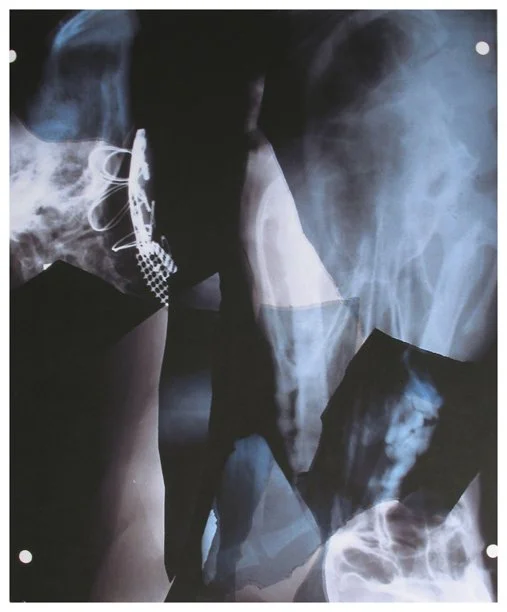

Insight is a series of collaged X-ray fragments, which were digitally composed into giclée prints. They speak not only of the body’s interior, but of the human experience it contains.

Drawn from DNA sequencing gels, mammograms, ultrasound scans, and cell cultures grown in Petri dishes, these compositions reframe diagnostic materials as metaphoric landscapes. What once served to identify illness becomes a language of line, texture, and light. They serve as a quiet meditation on fragility, resilience, and the unseen forces that shape us.

Each image in Insight is both an anatomical artifact and an artistic inquiry. Each one is part of my ongoing exploration of the relationship between Art, Science, and Medicine. Through digital layering and compositional play, I aim to dissolve the boundary between clinical detachment and emotional intimacy by inviting viewers to look inward and find meaning in the microscopic.